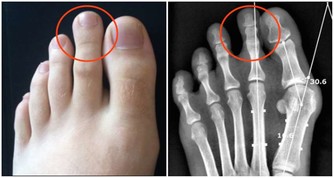

例如治療骨質疏鬆的阿崙膦酸鈉,由於其與食物和其他藥物可能存在較多的不良反應,

所以該藥應該於早晨在食物和其他藥物服用前至少半小時,用白開水送服。